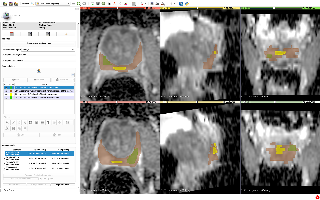

3D-IRCADB

| 3D-IRCADb 01 02 | 肝脏/肝肿瘤 | 分割 | CT | 20+2 | surface mesh | dcm | CC |

3D-IRCADb是比较早的一个数据集,有两个子集,分别包含20组和2组CT片子。